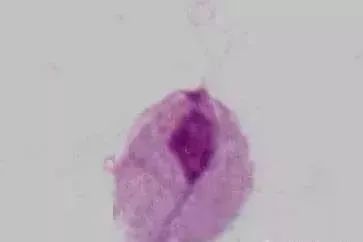

阴道毛滴虫

生理情况下,阴道pH为 -4.5,不适宜阴道毛滴虫生存 (其最适pH为5.5-6.0),故不引起女性生殖道滴虫性阴道炎。

病理情况下,滴虫可寄生于阴道后穹隆,常引起滴虫性阴道炎,可合并邻近器官的感染,如尿道和尿道旁腺感染。滴虫能利用上皮细胞内糖原作为能源,进行直接分裂,主要传播途径是通过衣物和性交。

男性中,滴虫可寄生于包皮下、前后尿道、前列腺 (最多见,占 90%)、精囊内,可长时间持续存在,具感染性,经直接或间接方法传播。阴道毛滴虫感染的发病率,在男性可达2%-15%,女性则达10%-25%。男性常为携带者。滴虫也引起泌尿道症状和不孕症。